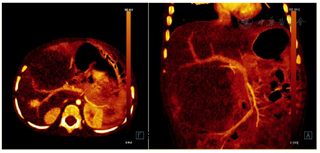

DECT采用选择性光子屏蔽(SPS Ⅱ)技术,在70kV和150kV的电压组合下实现能谱的显著分离。使用syngo.CT DE Virtual Unenhanced生成碘图/VNC融合图像,能显著提高血管和肿瘤的观察能力(图1和图2)。虚拟non-contrast(VNC)图像与常规平扫图像一致性匹配(图3),VNC可取代平扫,减少扫描次数做到降低总的剂量,提高合规管理和安全的儿童CT扫描使用。使用syngo.CT DE Monoenergy Plus,在这两个kV设置下获得的衰减值用于显示不同keV水平的图像。与在120kV下采集的常规CT图像相比,低keV的图像对比度显著增强,使得肿瘤侵犯的范围显示更加清晰(图4),低keV图像对比度是非常优异的(图5)。DECT的优势在于搭配西门子CT独有的水冷球管系统,双能力模式中两套球管独立工作,在同一辐射剂量的水平下,在不影响扫描流程和在不增加设备损耗的前提下,实现常规剂量成像,图像质量优异。70/Sn150kV的电压组合是目前用于儿童能量成像的最优参数设置。为了实现儿童低剂量能量检查,其他先进的技术也被使用,如CARE Dose 4D(实时自动曝光控制)和ADMIRE(高级模型迭代重建)。在本病例中,儿童多期CT检查,其中平扫、动脉期和静脉期用双能量技术,延迟期用自由呼吸大螺距技术,多期联扫总的辐射剂量仅为2.85mSv,为传统CT检查的2/5。